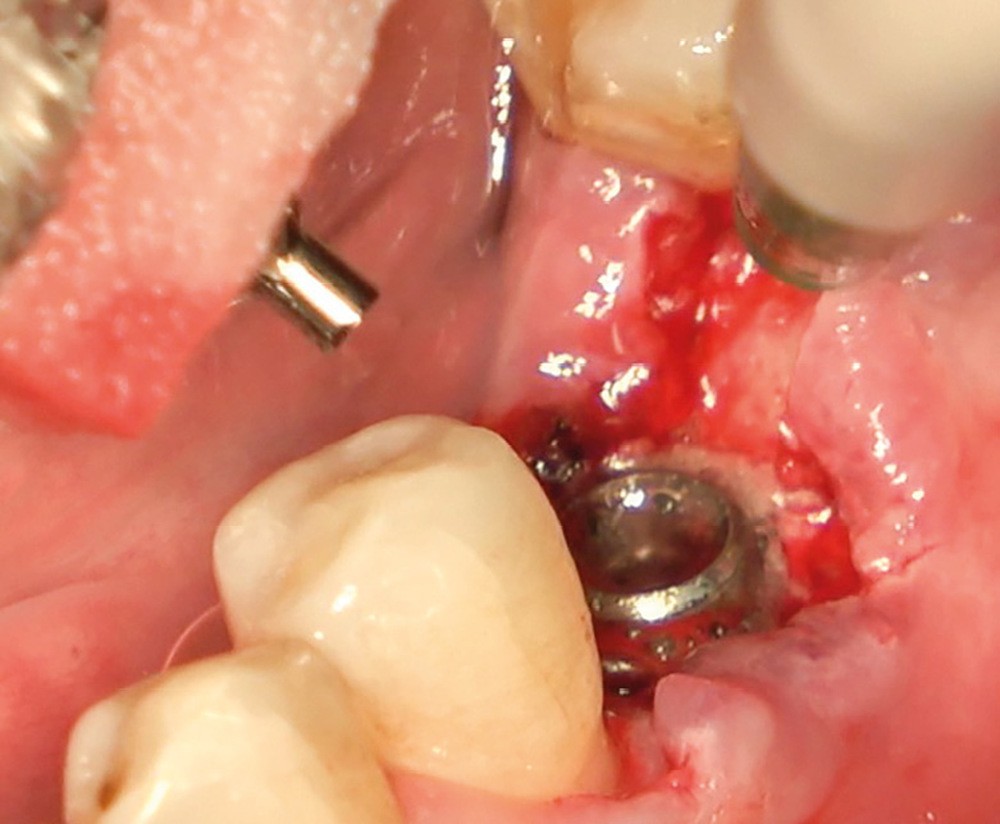

- Avulsion de la 36 et régénération osseuse guidée (ROG) réalisée en 2017 suite à une fracture de la dent et une infection

- Un implant posé en 2018 après la fin du traitement orthodontique

- Péri-implantite diagnostiquée en 2021